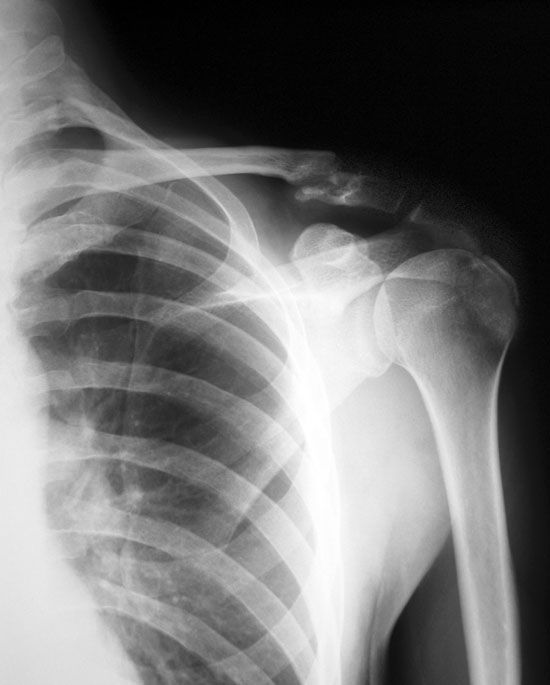

Radiograph of the left shoulder showing normal appearance. | Download …

NORMAL SHOULDER 3 | buyxraysonline

Normal Shoulder X Ray Left – slidesharedocs

Shoulder x-ray (AP)